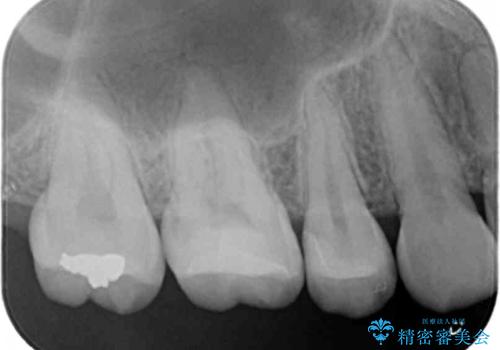

2歯とも白くて適合の良いセラミックインレーでの修復をすることとなりました。

まだ虫歯が大きくなる前に処置をすることができたため神経の治療をせずに済みました。

修復物と歯の間の虫歯は、丁寧な虫歯除去と精密な修復物を装着することで予防することができます。